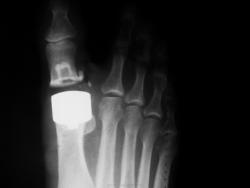

Один из методов лечения поперечного палоскостопия с выраженым дефартрозом 1 пл-ф суст. Операция Вредена-Мейо+ операция Брандеса+формирование поперечной связки стопы+протезирование. Померяйте какой сейчас Hallux valgus, опишите состояние культи и протеза.

Уважаемая Медея(вот красивое имя у Вас), к сожалению с протезированием данного сустава я не сталкивался, скажите Вы выставили первичный снимок до операции ( вальгус там не большой), какие причины сподвигли докторов заменить сустав? боль? нарушение опоры, ходьбы?у Вас это рядовая операция или "будем пробовать" , с таким варусом сложно обувь подобрать, поперечный свод стопы стал еще шире.....

2. Трактуйте картину какова она есть, желательно - как можно детальнее. Как там с отеком еще будет: спадет- не спадет, восстановится ось - не восстановиться - Вы свое дело сделали, а это главное.